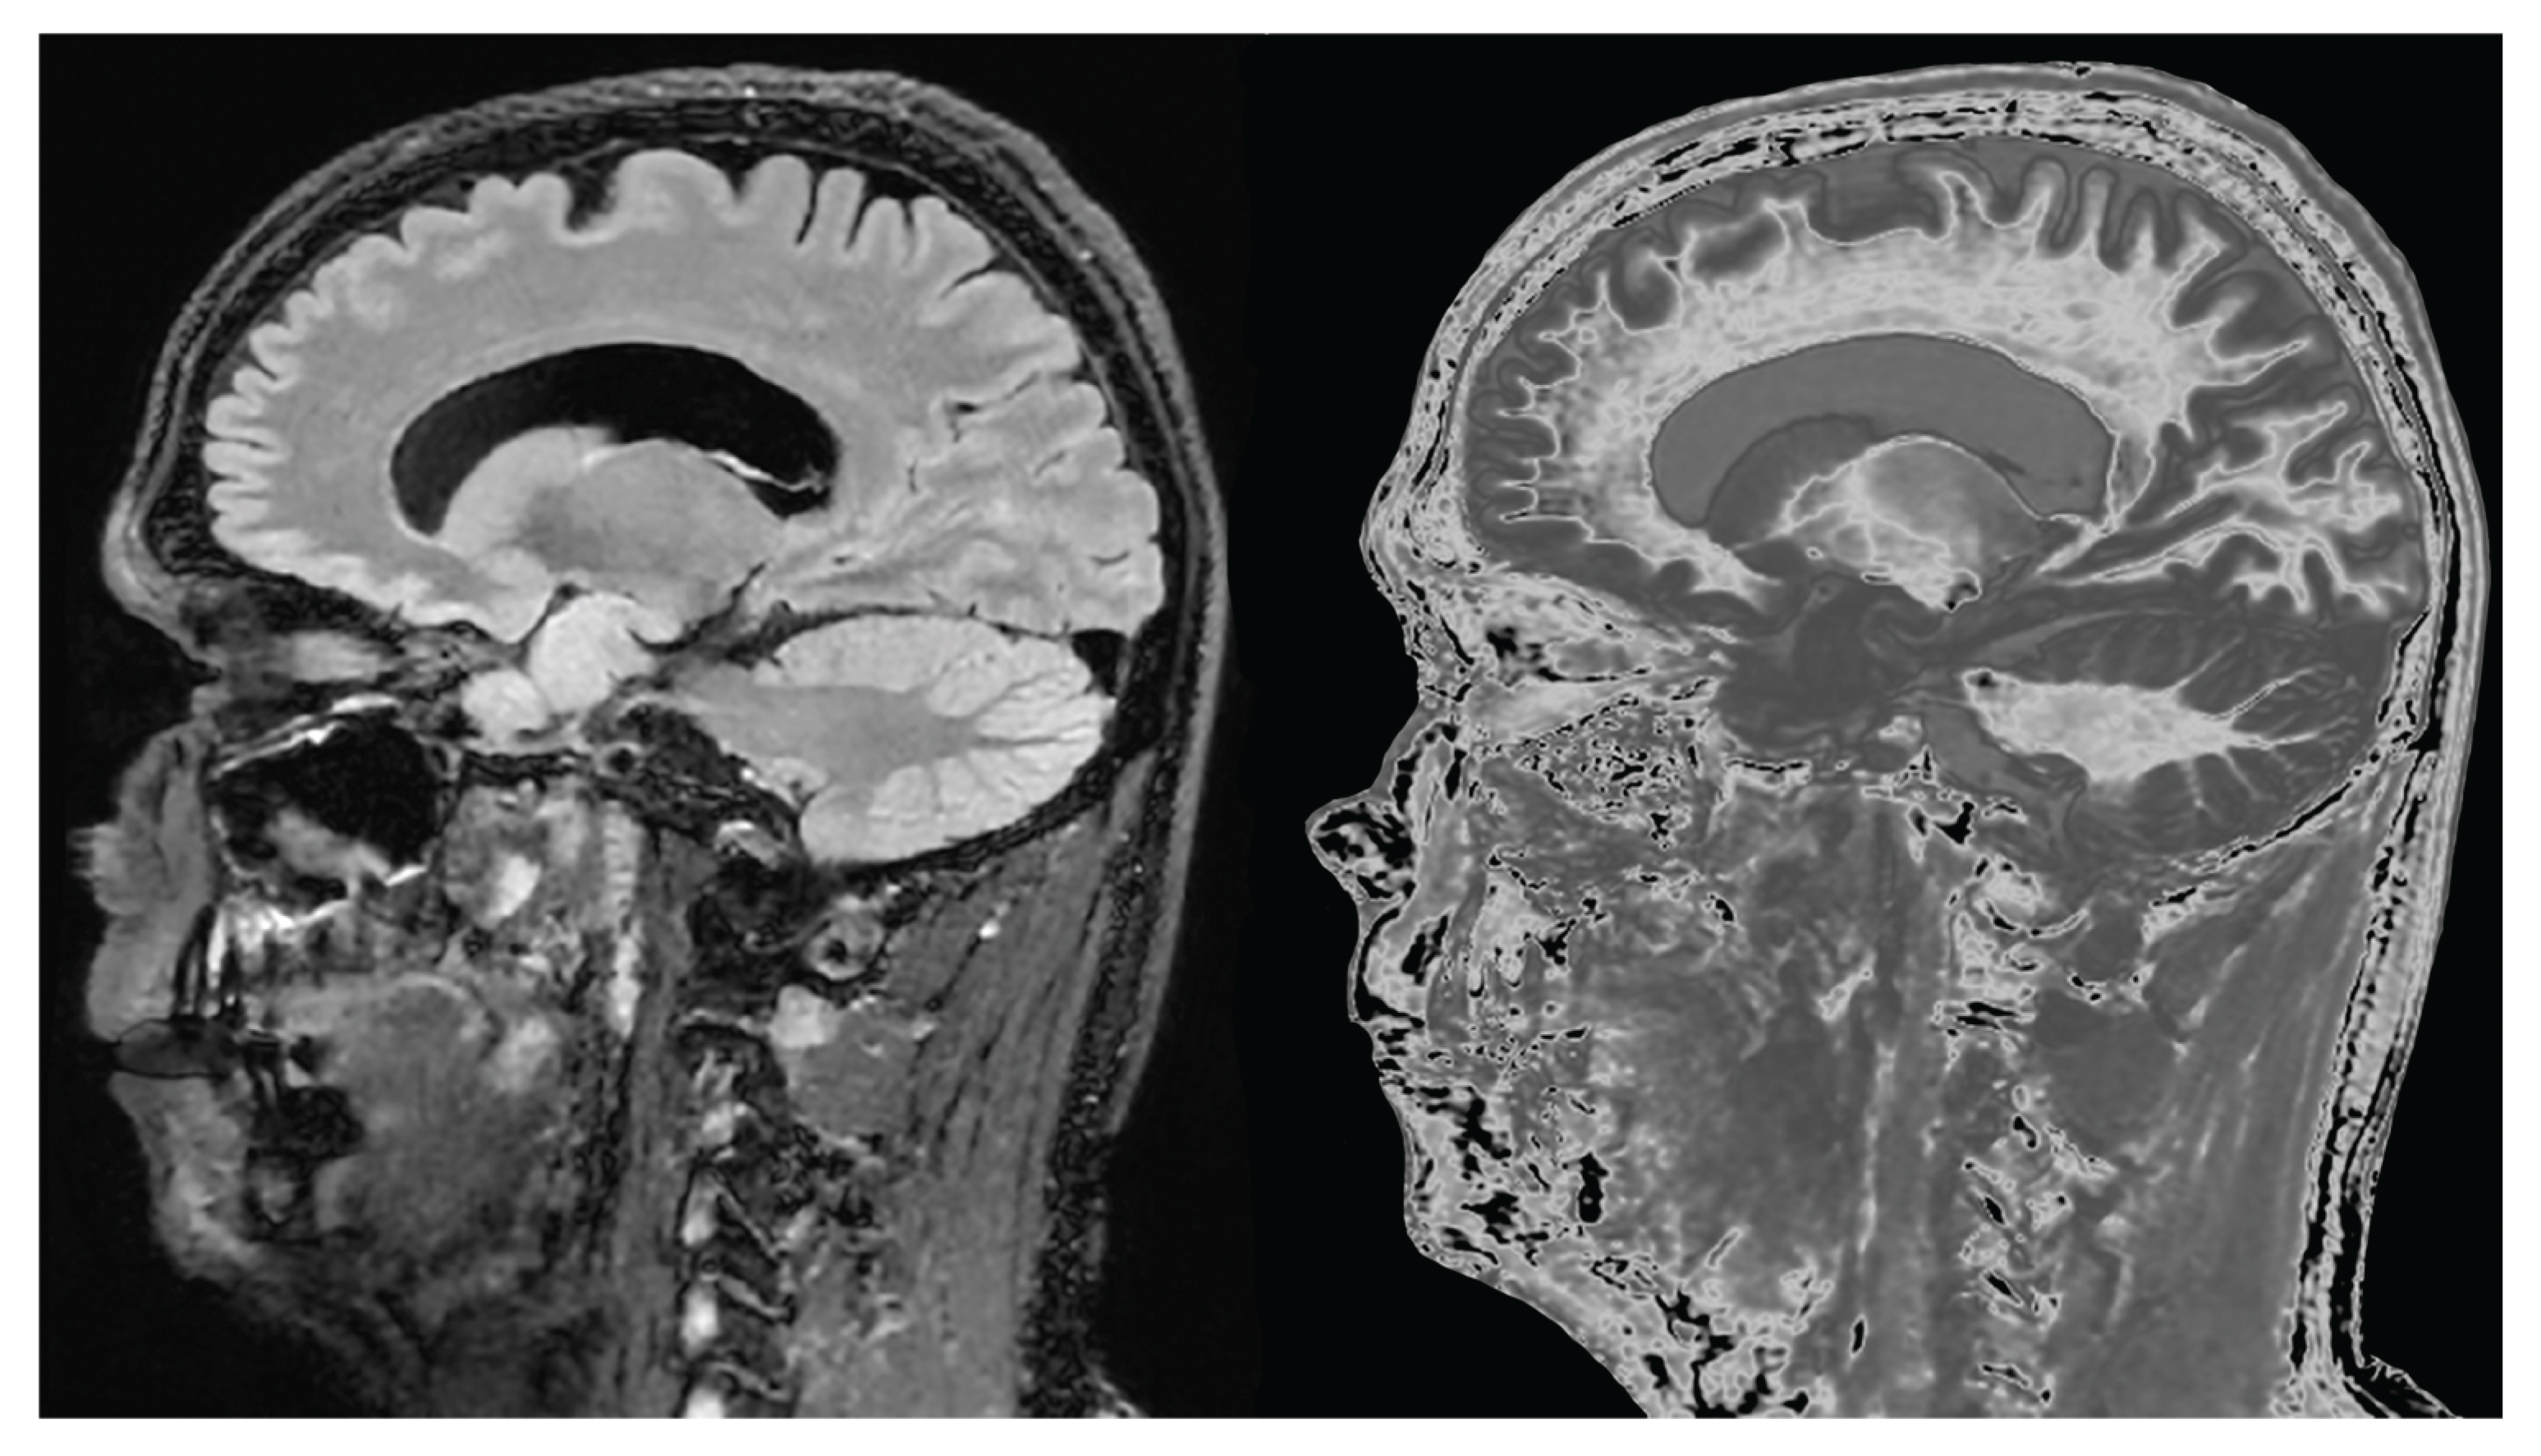

- Mild Traumatic Brain Injury (mTBI)

- Normal Control and MS Patient with dSIR and lSIR Images